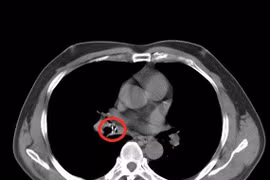

Trong quá trình mổ, các bác sĩ phát hiện ruột non của bé trai bị thủng 8 lỗ, dị vật đã rỉ sét bám dính gây hoại tử.